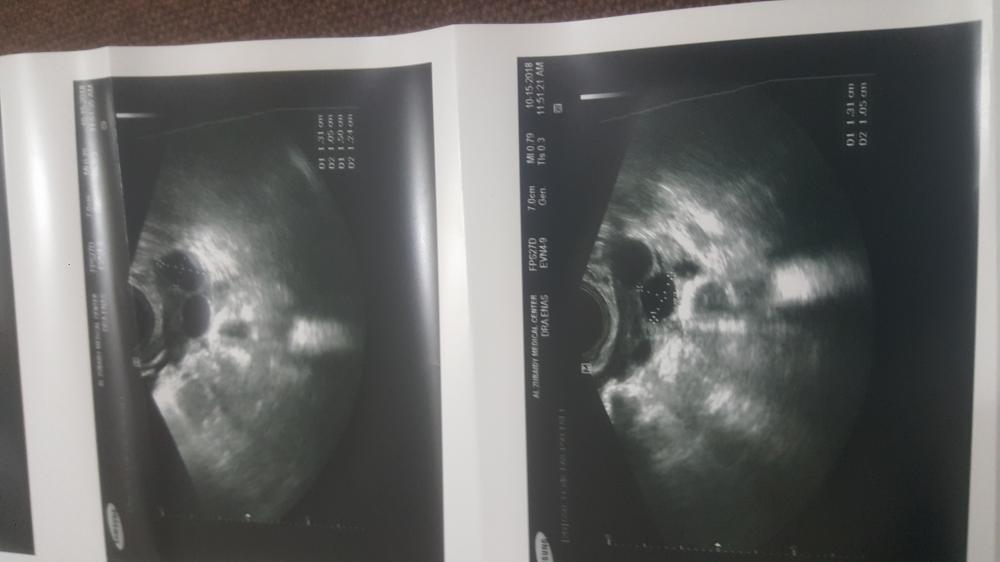

وهاذي ابنتايج وقالت لي ٣ بالمبيض واضحين وحجمهم كويس بالمبيض الايمن ... والايسر مافيه شي

لكن احجامهم ماني بذاكرة كم وهاذي النتايج علموني .

وبطانة الرحم ٦